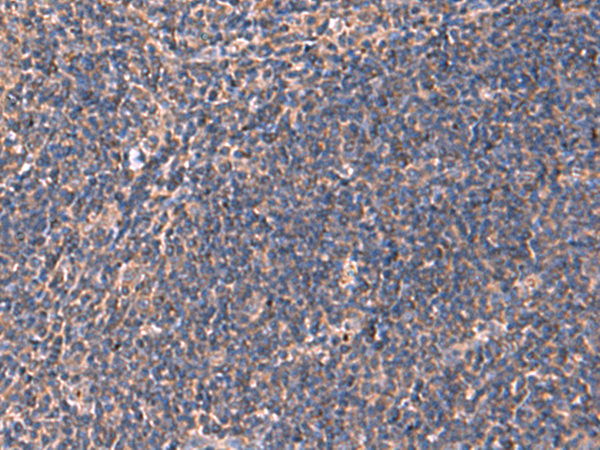

分类: 科研抗体货号: P10170别名: NML; KIAA0409应用: WB,IHC反应种属: Human, Mouse, Rat